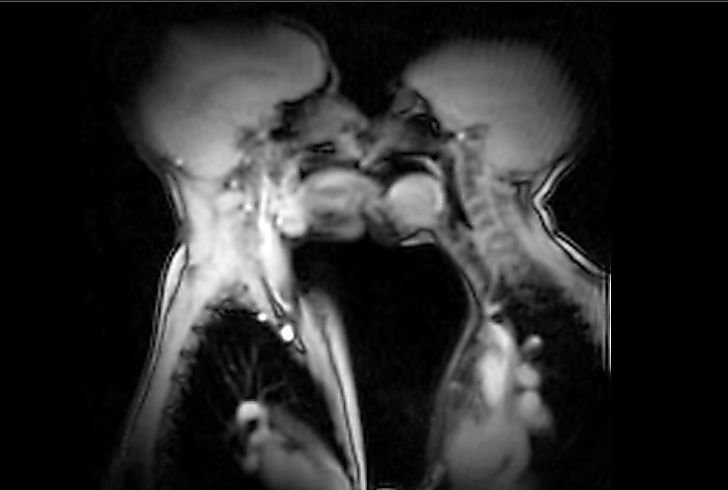

Holenderskim naukowcom udało się zrobić nagranie pary całującej się i uprawiającej seks podczas badania rezonansem magnetycznym (MRI). W 2000 roku zostali za to nagrodzeni nagrodą Ig Nobla – przyznawanej co roku "za odkrycia, które najpierw śmieszą, a potem skłaniają do myślenia".